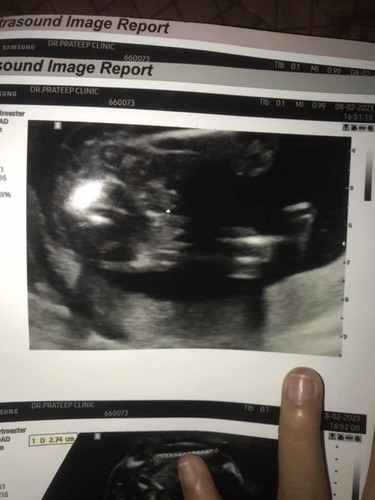

อยากสอบถามแม่ว่าในรูปซาว น้อง เป็นผญหรือผชค่ะ แต่หมอบอกผชอิแม่มองไม่ออกเลย ว่าเป็นผู้ชาย

น่าจะผู้ชายนะคะแม่ ยื่นออกมาขนาดนั้น55 ไม่น่าจะเป็นจิมิแล้วคะ🤣🤣

อิแม่ไปหาหมอมื้อวาน บอก ก็ตอบคำเดิมว่าผช แล้ว ไข่ใหญ่มาก

ของลูกเราชัดมาก ตอน 22วีค กระจู๋ไข่มาเต็มๆเลย

เราว่า ผช ค่ะ ถ้าผญ หมอบอกจะแบนๆราบๆเลยค่ะ

ผช ชัดมากค่ะแม่ ของเราก็แบบแม่เลย

เชื่อหมอได้เลยค่ะผู้ชายชัวร์ 100%

เรามองว่าเป็นกลีบผู้หญิงนะคะ